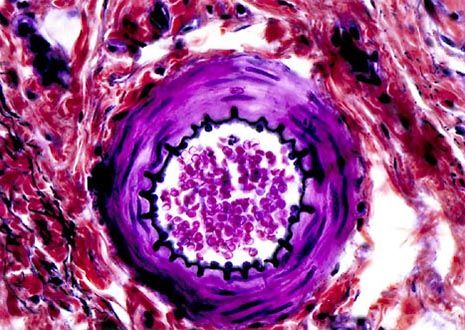

The vascular system is one of the first developments in an embryo because transporting fluids is a fundamental need of growing life forms. As components of the vascular system, arterioles are small tubes that branch from arteries and are important in the conveyance of blood.